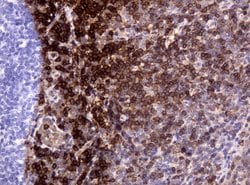

CD3 Mouse anti-Human, Clone: UMAB54, liquid, UltraMAB™

Mouse Monoclonal Antibody

Brand: Origene Technologies UM500048

CD3 epsilon is part of the CD3 subunit complex which is crucial in transducing antigen-recognition signals into the cytoplasm of T cells and in regulating the cell surface expression of the TCR complex. T cell activation through the antigen receptor (TCR) involves the cytoplasmic tails of the CD3 subunits CD3 gamma, CD3 delta, CD3 epsilon and CD3 zeta. These CD3 subunits are structurally related members of the immunoglobulins super family encoded by closely linked genes on human chromosome 11. The CD3 components have long cytoplasmic tails that associate with cytoplasmic signal transduction molecules and this association is mediated at least in part by a double tyrosine-based motif present in a single copy in the CD3 subunits. CD3 may play a role in TCR-induced growth arrest, cell survival and proliferation. The CD3 antigen is present on 68-82% of normal peripheral blood lymphocytes, 65-85% of thymocytes and Purkinje cells in the cerebellum. It is never expressed on B or NK cells. Decreased percentages of T lymphocytes may be observed in some autoimmune diseases. The genes encoding the CD3 epsilon, gamma and delta polypeptides are located on chromosome 11. Defects in this gene are associated with T cell immunodeficiency and has been linked to Type 1 Diabetes deficiency in women.Specifications

| Immunocytochemistry, Immunofluorescence, Immunohistochemistry (Paraffin) | |

| UMAB54 | |

| Full length human recombit protein of human CD3E produced in HEK293T cell. | |